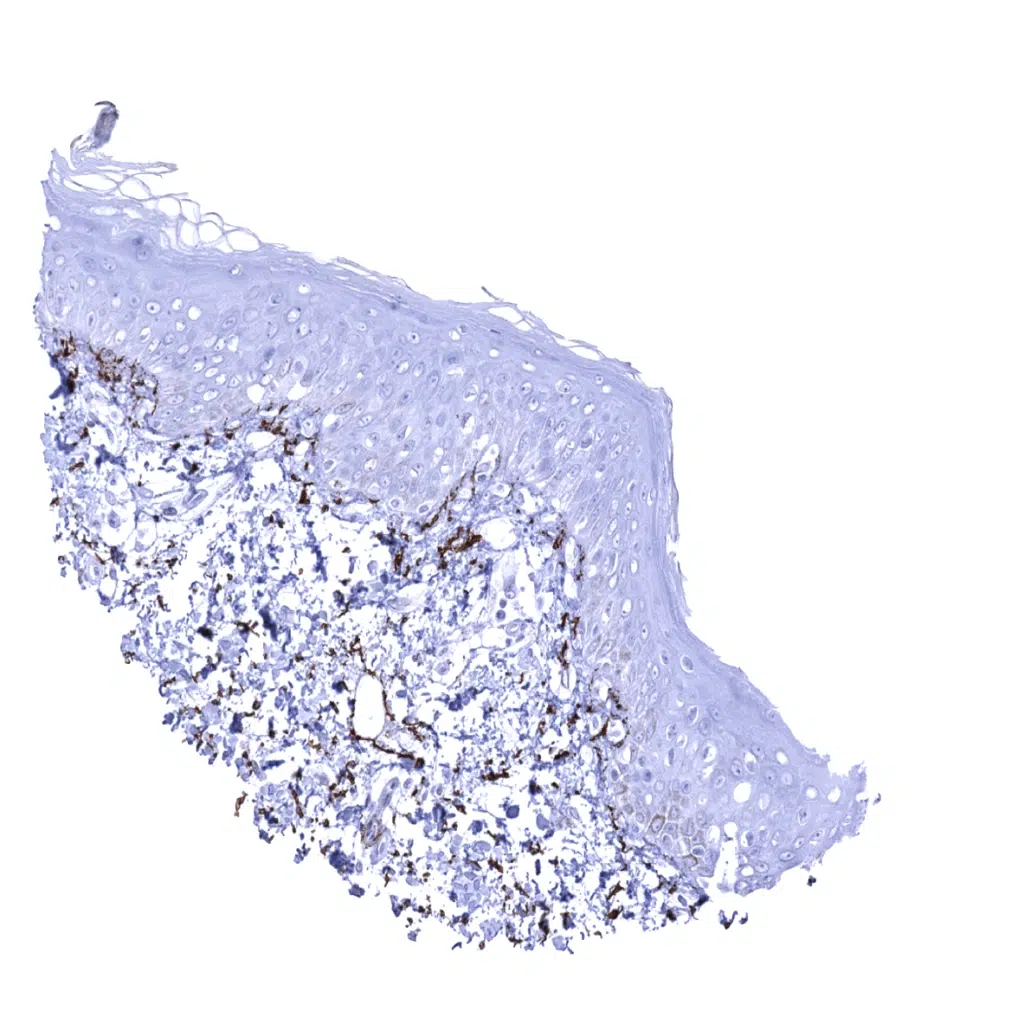

Skin – Elastin fibres occur below the epidermis.